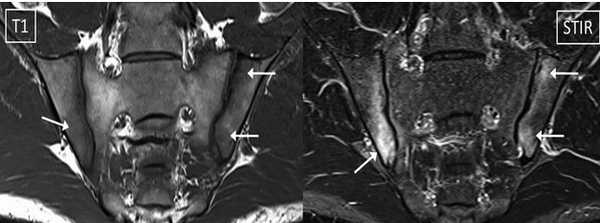

МРТ крестцово-подвздошных суставов - типичный воспалительный сакроилеит при аксиальном спондилоартрите (стрелки)

В норме крестцово-подвздошные сочленения обычной конфигурации, симметричны с обеих сторон, ширина не изменена. Костно-суставные взаимоотношения не нарушены, периартикулярные и пресакральные ткани без видимых изменений. Краевых остеофитов, отека, деформации нет. Пояснично-крестцовый переход и видимые крылья подвздошных костей без особенностей. Позвоночные сакральные отверстия симметричны, не расширены.

МРТ: двусторонний склероз подвздошной кости с сужением суставной щели (стрелка)